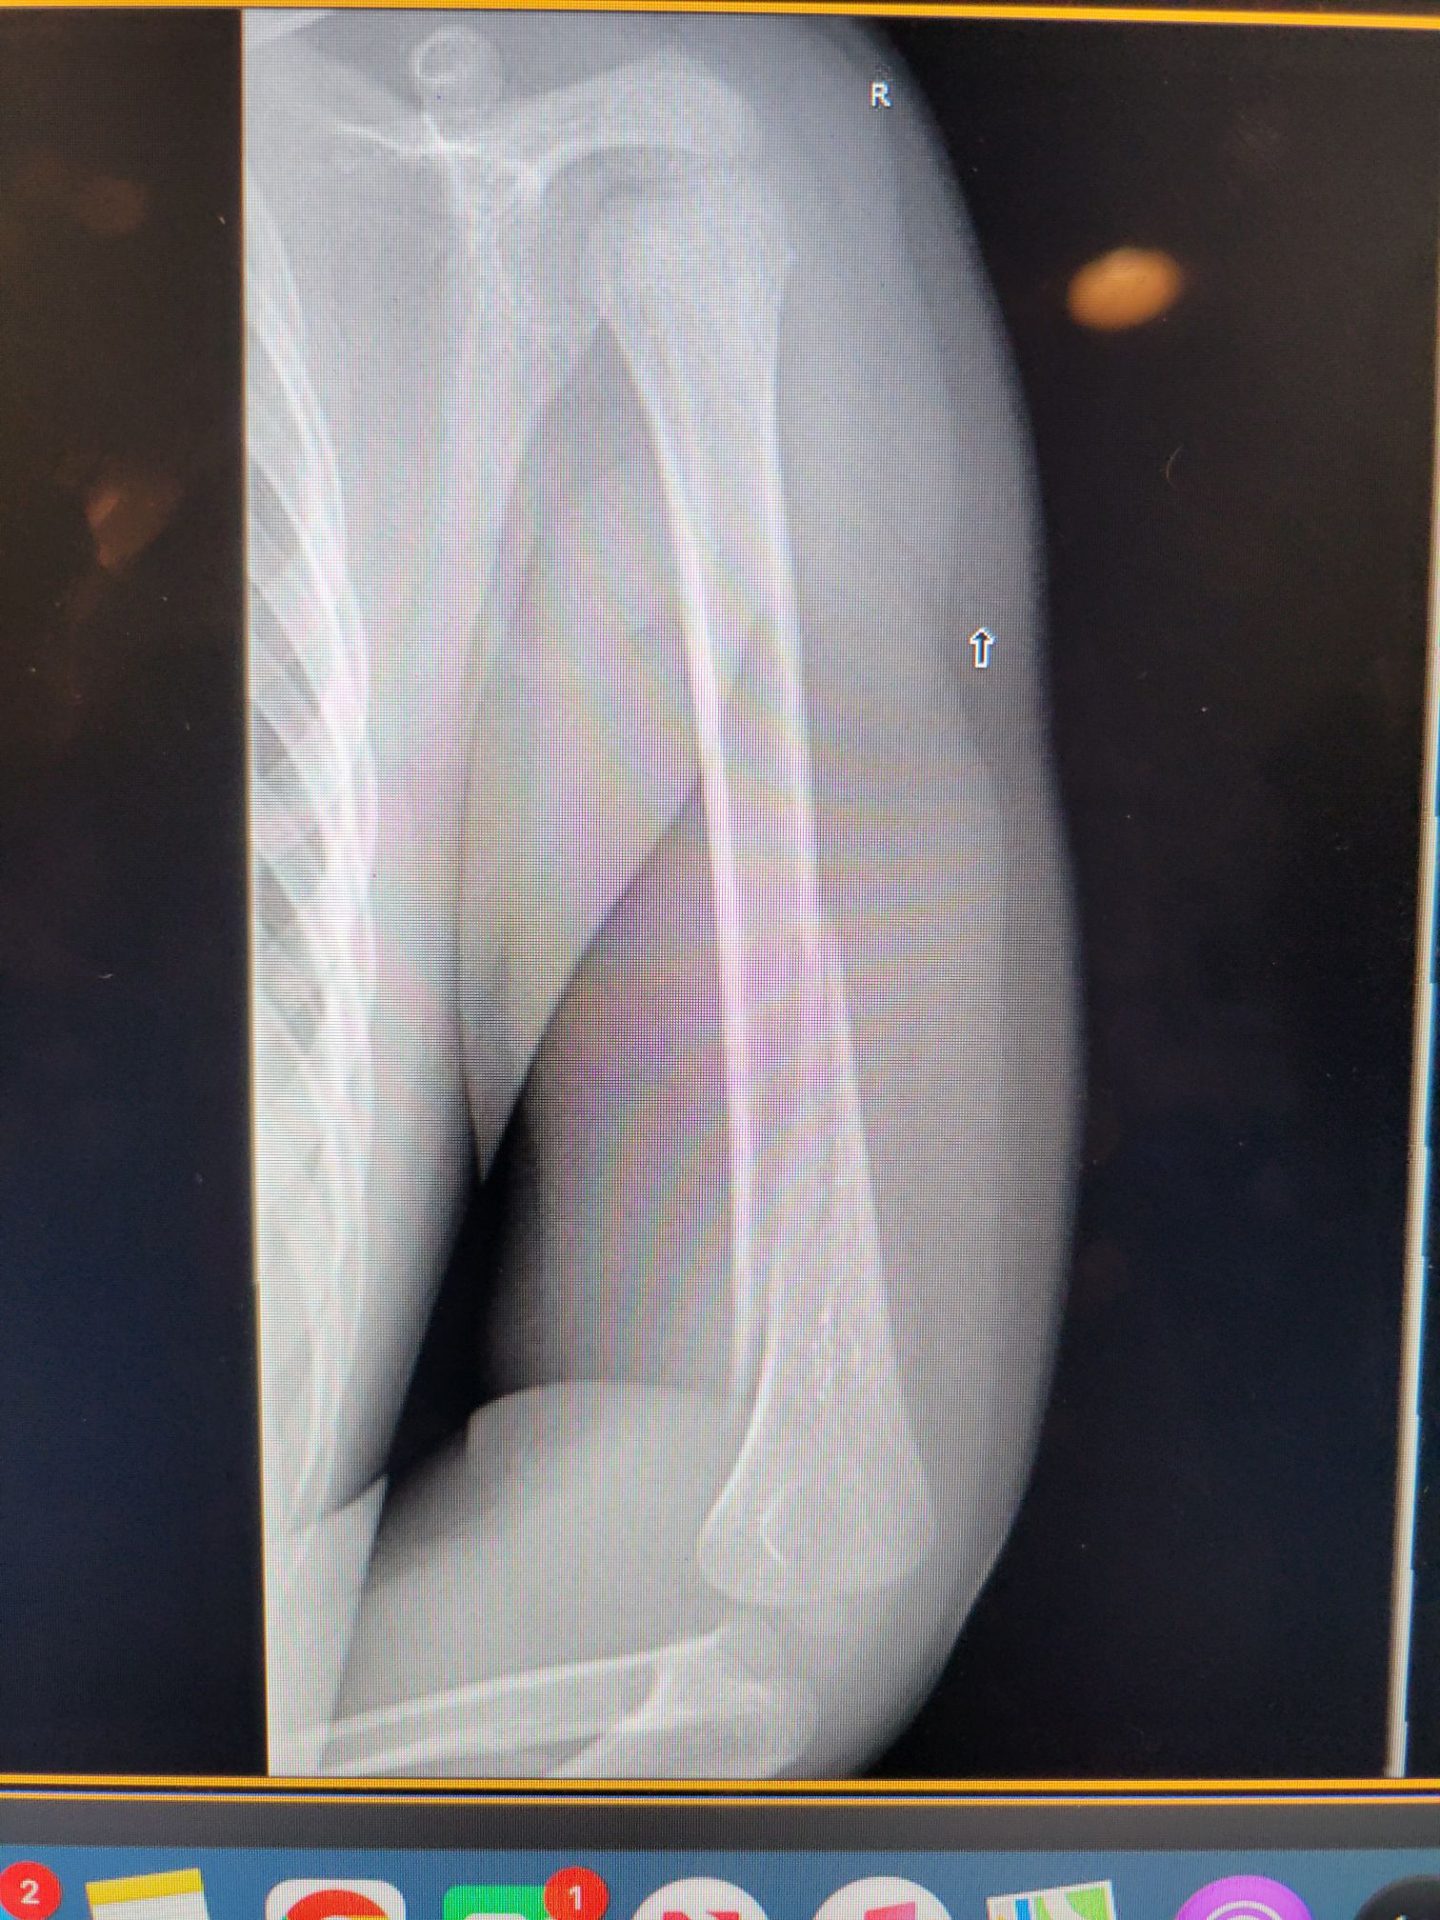

Great morning riding in Morro Bay at the beach with Sierra. However, Dunny thought he saw a sea monster in the waves and unexpectedly skedaddled out of the water in a hurry. Cato held on for a while but then hit the sand hard. The nice Urgent Care, ER, and Orthopedic Surgeon office staff were all great helping us with his broken arm, and Cato’s been a serious trooper! He was especially intrigued with being inside a monster donut!